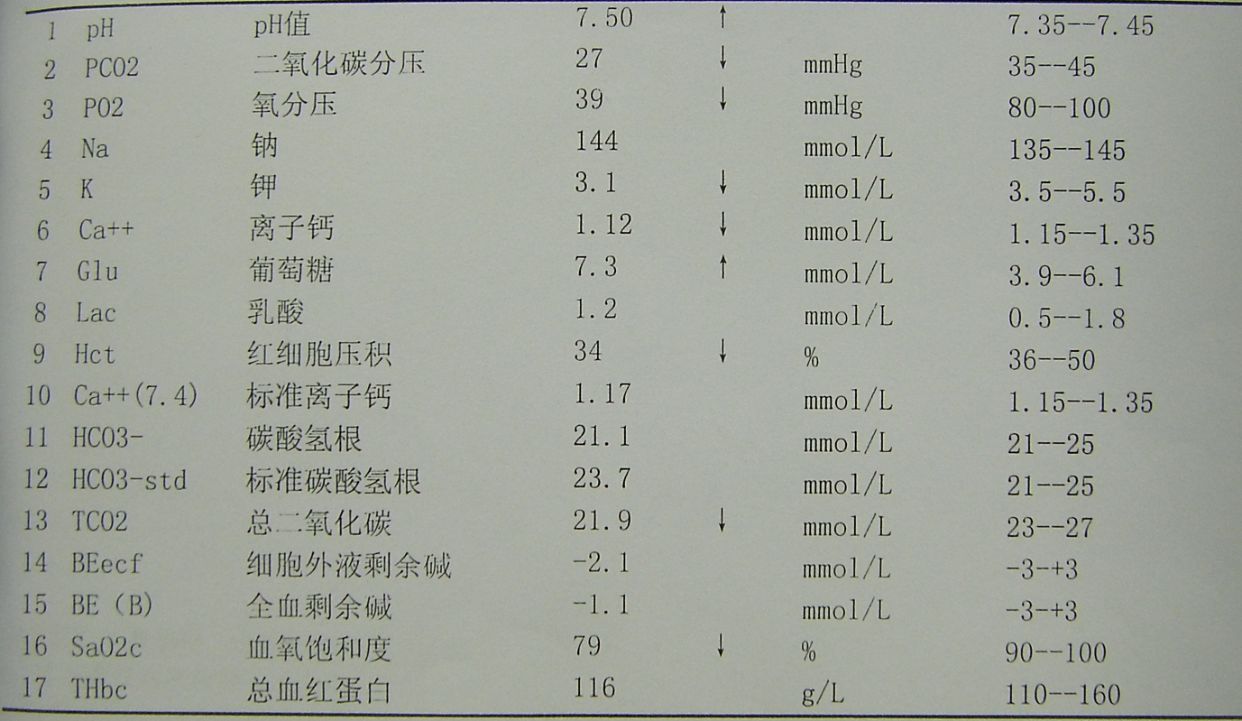

查血气分析示,丨型呼吸衰竭并呼碱,给予呼吸机辅助呼吸。